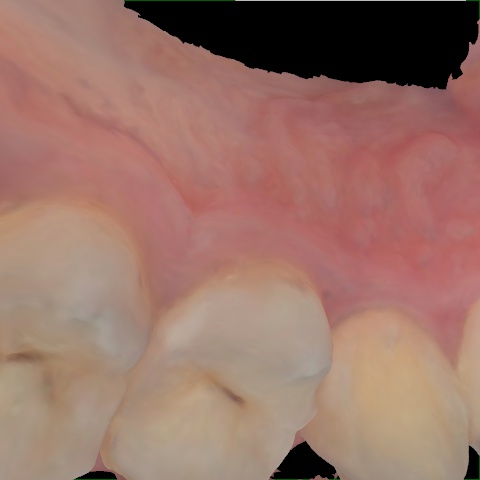

Incorrect Quality Level

The reference annotation for this image is

None

.

Please select the correct quality level.

Annotated as "Good"